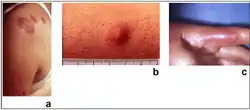

| Sweet syndrome lesions with the classical form of the dermatosis. | |

Sweet syndrome (SS), or acute febrile neutrophilic dermatosis,[1][2] is a skin disease characterized by the sudden onset of fever, an elevated white blood cell count, and tender, red, well-demarcated papules and plaques that show dense infiltrates by neutrophil granulocytes on histologic examination.

Acute, tender, erythematous plaques, nodes, pseudovesicles and, occasionally, blisters with an annular or arciform pattern occur on the head, neck, legs, and arms, particularly the back of the hands and fingers. The trunk is rarely involved. Fever (50%); arthralgia or arthritis (62%); eye involvement, most frequently conjunctivitis or iridocyclitis (38%); and oral aphthae (13%) are associated features.